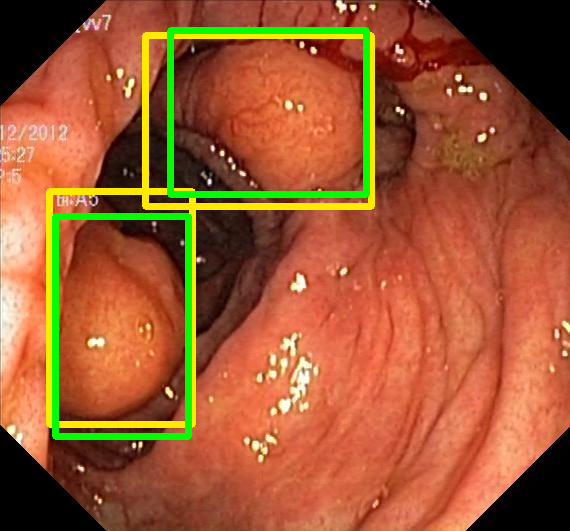

We evaluate the resulting object detection models using the test data, which is pre-processed in the same manner as the validation data, with AP@[.5:.95] (AP for conciseness), AP@.5 (AP50), and AP@.75 (AP75) computed for predicted bounded boxes with a confidence score \geq0.05. For all metrics, a higher value indicates better performance. The results are presented in Table VI, and some examples for predicted bounding boxes with a confidence score \geq0.5 are shown in Fig. 1.

Figure 1: Targets (yellow bounding boxes) and predictions (green bounding boxes) for two randomly selected instances of the Kvasir-SEG test set. For conciseness, we denote ResNet50s with RN, ViT-Bs with VT, Hyperkvasir-unlabelled with HK, ImageNet-1k with IN, MoCo v3 with MC, Barlow Twins with BT, MAE with MA, supervised pretraining with SL, and no pretraining with NA-NA.